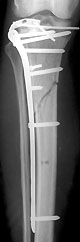

Oft musste ich lachen, wenn ich Deine 'Ausschmückungen' las. Genauso hätte ich es auch geschildert. Es stimmt einfach alles, sogar die Namen der Ärzte. Prof. Leutenegger hat mich noch kurz vor seiner Pensionierung in Empfang genommen und mir die aufbauende Nachricht meiner Tibiakopftrümmerimpressionsfraktur (welch schönes Wort), Schien- und Wadenbeinbruch, Meniskusabriss und zu guter Letzt nur noch eine kleine Bänderzerrung am Fussgelenk (die erst viel später diagnostiziert wurde - peanuts) überbracht. Von Dr. Sommer wurde ich dann - nach einer Woche mit Fixateur externe - operiert. Nähen kann der Mensch! Alle Leute bewundern meine schöne 20 cm lange Narbe.

Nun bin ich allerdings in einem Geduldstief. Anfangs Juli war ich zur Kontrolle im Kantonsspital Chur. Dr. Sommer gab mir da grünes Licht, in der Wohnung ohne Krücken oder zumindest nur mit einer zu gehen. Das ging anfangs ja noch ganz gut. Die Schmerzen im Schienbein wurden aber beim Auftreten immer heftiger und das Bein war auch ständig über-wärmt. Also wurde ich von meiner Hausärztin an einen Spezialisten weiter gewiesen. Da hiess es dann, wieder mit beiden Krücken gehen und nur noch 20kg belasten. Zwei Tage später ging es mir aber tatsächlich wieder besser.

Nun muss ich Ende August nochmals zum Röntgen - und dann werden wir sehen, ob sich Schien- und Wadenbein so weit konsolidiert haben, damit ich wieder mit der Mehrbelastung beginnen kann. Ich hoffe, dass ich irgendwann wieder einmal ohne Schmerzen gehen kann. Momentan kann ich es mir wahrlich nicht vorstellen. Oder wieder einmal eine Treppe normal hinauf gehen (es müssen nicht gleich zwei Tritte aufs Mal sein - ich bin ja bescheiden). Diesen Winter werde ich vermutlich meine Ferien irgendwo in Florida verbringen statt in meinem geliebten Tschiertschen. Allen Tibiaköpflern wünsche ich viel Kraft und Geduld!